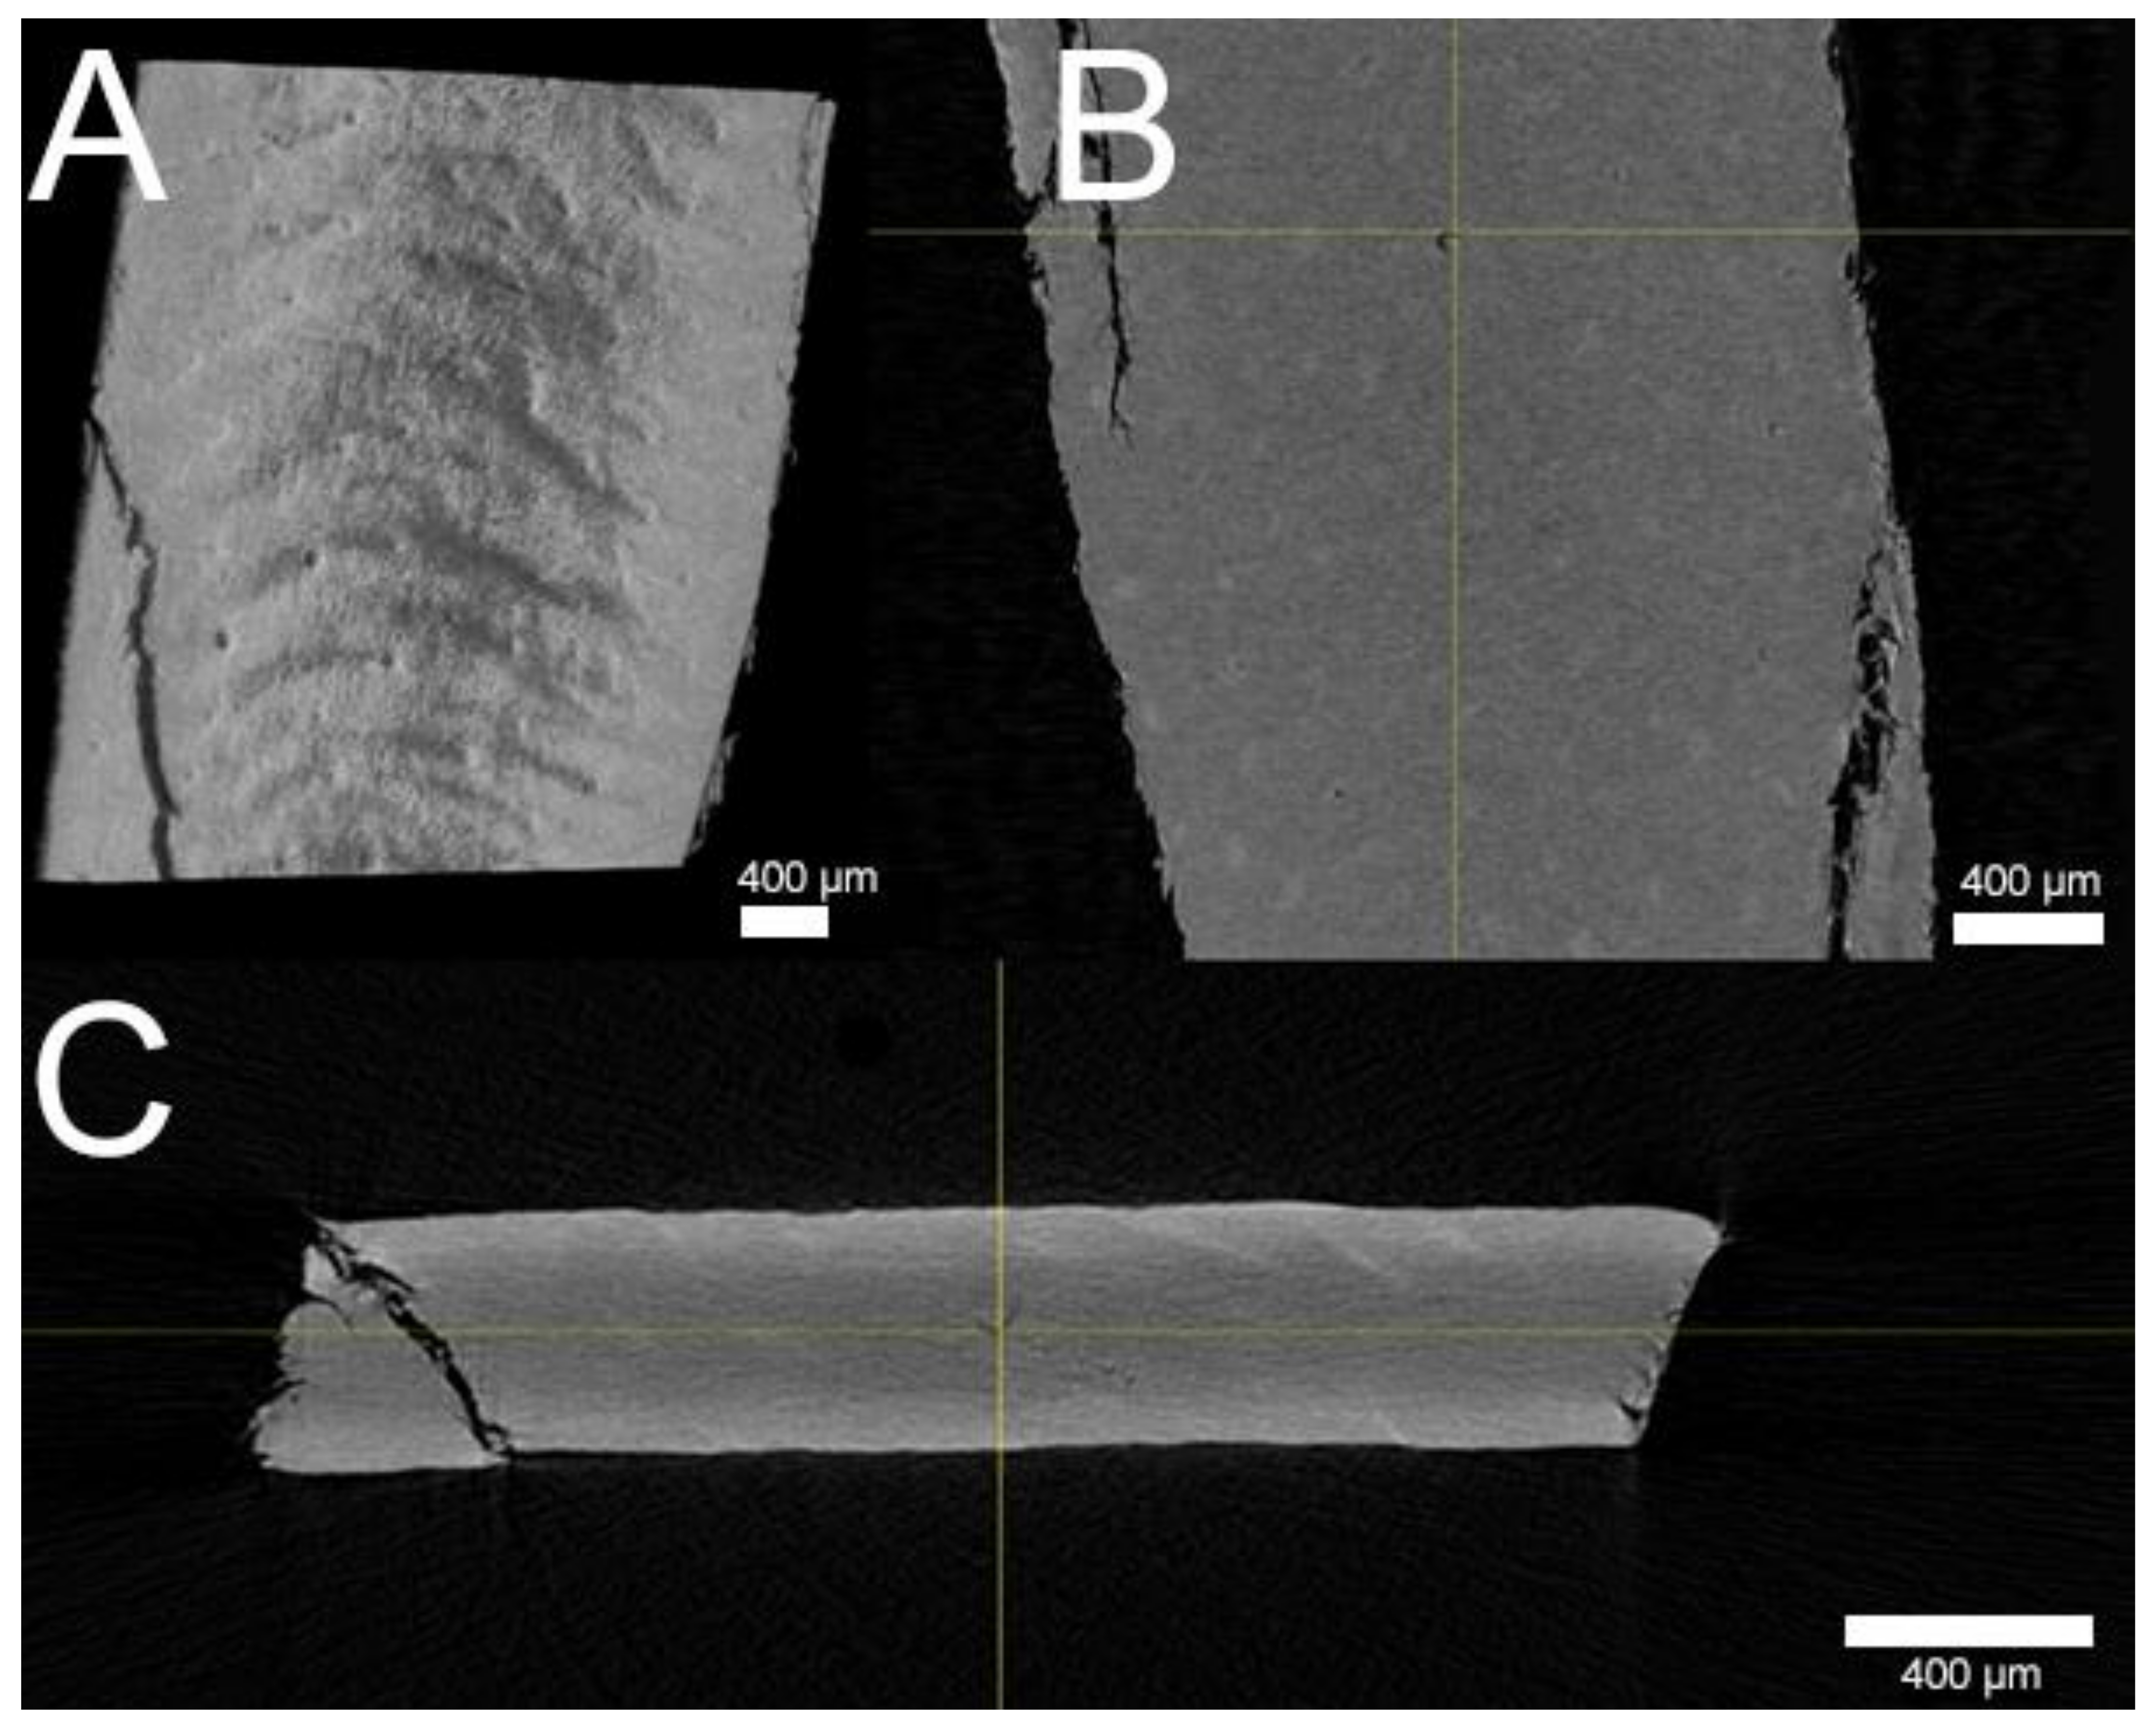

Figure 2.

Volume rendering of x-ray microtomography bovine hoof sheet (BHS) images. (A) Surface of BHS in the Y-direction with various porous cavities visible. (B) Focused hollow pore (yellow cross) inside the BHS matrix in the Y-direction and (C) Z-direction, revealing continuation of the pore as a dark crack from the top left to bottom right; each scale bar = 400 µm.

µCT and SEM images depicted a smooth-to-wavy surface texture with a multitude of porous structures on the membrane’s surface (Figure 1A,B). Some structures on the surface appeared to be during in SEM, while some were visibly open, with a diameter of up to roughly 50 µm. Further examination by µCT revealed pores extending coherently throughout the whole membrane transversally as brighter areas against the darker keratin matrix (Figure 2B,C). Exemplary focusing of such a pore in the middle of the membrane’s diameter (yellow cross) showed a hollow area visible from each axis that continued transversally as a dark crack. Further FIB milling of the matrix around these pores and the subsequent imaging of the resulting cross-section revealed that, although pores may seem to be closed or superficial, hollow structures continued beneath the surface, connecting to deeper membrane layers (Figure 1B). SEM imaging of the infected BHS showed the dense, superficial growth of fungal hyphae, completely covering the membrane’s surface (Figure 3A). Imaging of a fracture cross-section revealed that fungi also grew into the membrane (Figure 3B).

When implementing BHS as a surrogate model for human nails, Mertin and Lippold found BHS to be less dense, with an increased swelling capacity compared to human nails, resulting in a higher permeability [15]. However, upon verifying the integrity of their membranes via SEM imaging, they stated an absence of pores but existence of cavities [13]. In contrast to their findings, using the FIB milling technique combined with SEM imaging, these cavities were shown not to be superficial but connect to deeper membrane levels. The additional investigation of these structures with µCT imaging further confirmed the existence of connected, transversally proceeding hollow cracks. The porosity of BHS and human nails was investigated by Nogueiras-Nieto et al. using mercury intrusion porosimetry [16]. Agreeing with our findings, their study showed that dry BHS had a pronounced porosity at the surface; yet, the internal structure of BHS had a low porosity. The hydration of both human nails and BHS increased the porosity and interconnection of the keratinous network. As revealed by our imaging, the decline of porosity in the deeper membrane levels in these studies might be due to a blockade of porous tunnels by keratinous debris. The properties of bovine claw horn were investigated by Baillie et al. [17]. Using a light microscope, they demonstrated continuous tubules running through the bovine hoof, which were shown to be hollow in SEM fracture specimens by Wang et al. [18]. Despite the hydration, freezing, and cutting steps in preparation of the BHS, these tubules were not closed, as revealed by µCT and FIB-SEM. Thus, it is very likely that channels filled with the receiver medium are present in FDC experiments. These channels presumably act as shunt routes, facilitating permeations. Therefore, an increased membrane thickness might reduce the effect of such routes through the increased chance of debris in tubules and a longer route of diffusion for APIs and subsequently lead to more appropriate datasets than with thinner BHS.